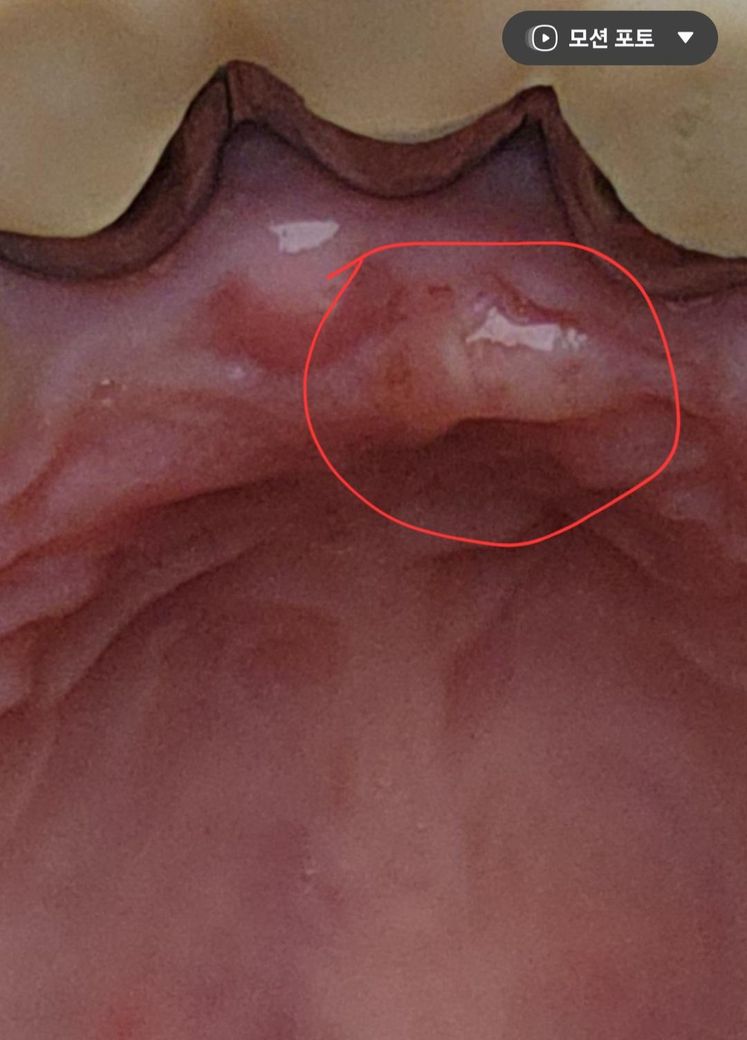

잇몸 입천장쪽에 생긴 이것은 무엇일까요~?

잇몸 입천장쪽에 생긴 이런게 생겼습니다.

생긴지는 한달정도 된것 같은데 혹시 무엇일까요~?

• 2번 째 사진

입천장이 자극을 받아서 생긴 염증일수도 잇지만 치아때문에 생긴 염증일수도 잇으니 치과에 가셔서 일단 치과에 가셔서 엑스레이를 찍어보시는게 좋을것같습니다

사진상 농양이 생긴 것으로 보입니다. 씌운 치아가 신경치료가 되어 있다면 재신경치료, 신경치료가 안되어 있다면 신경치료가 필요할 수 있겠습니다